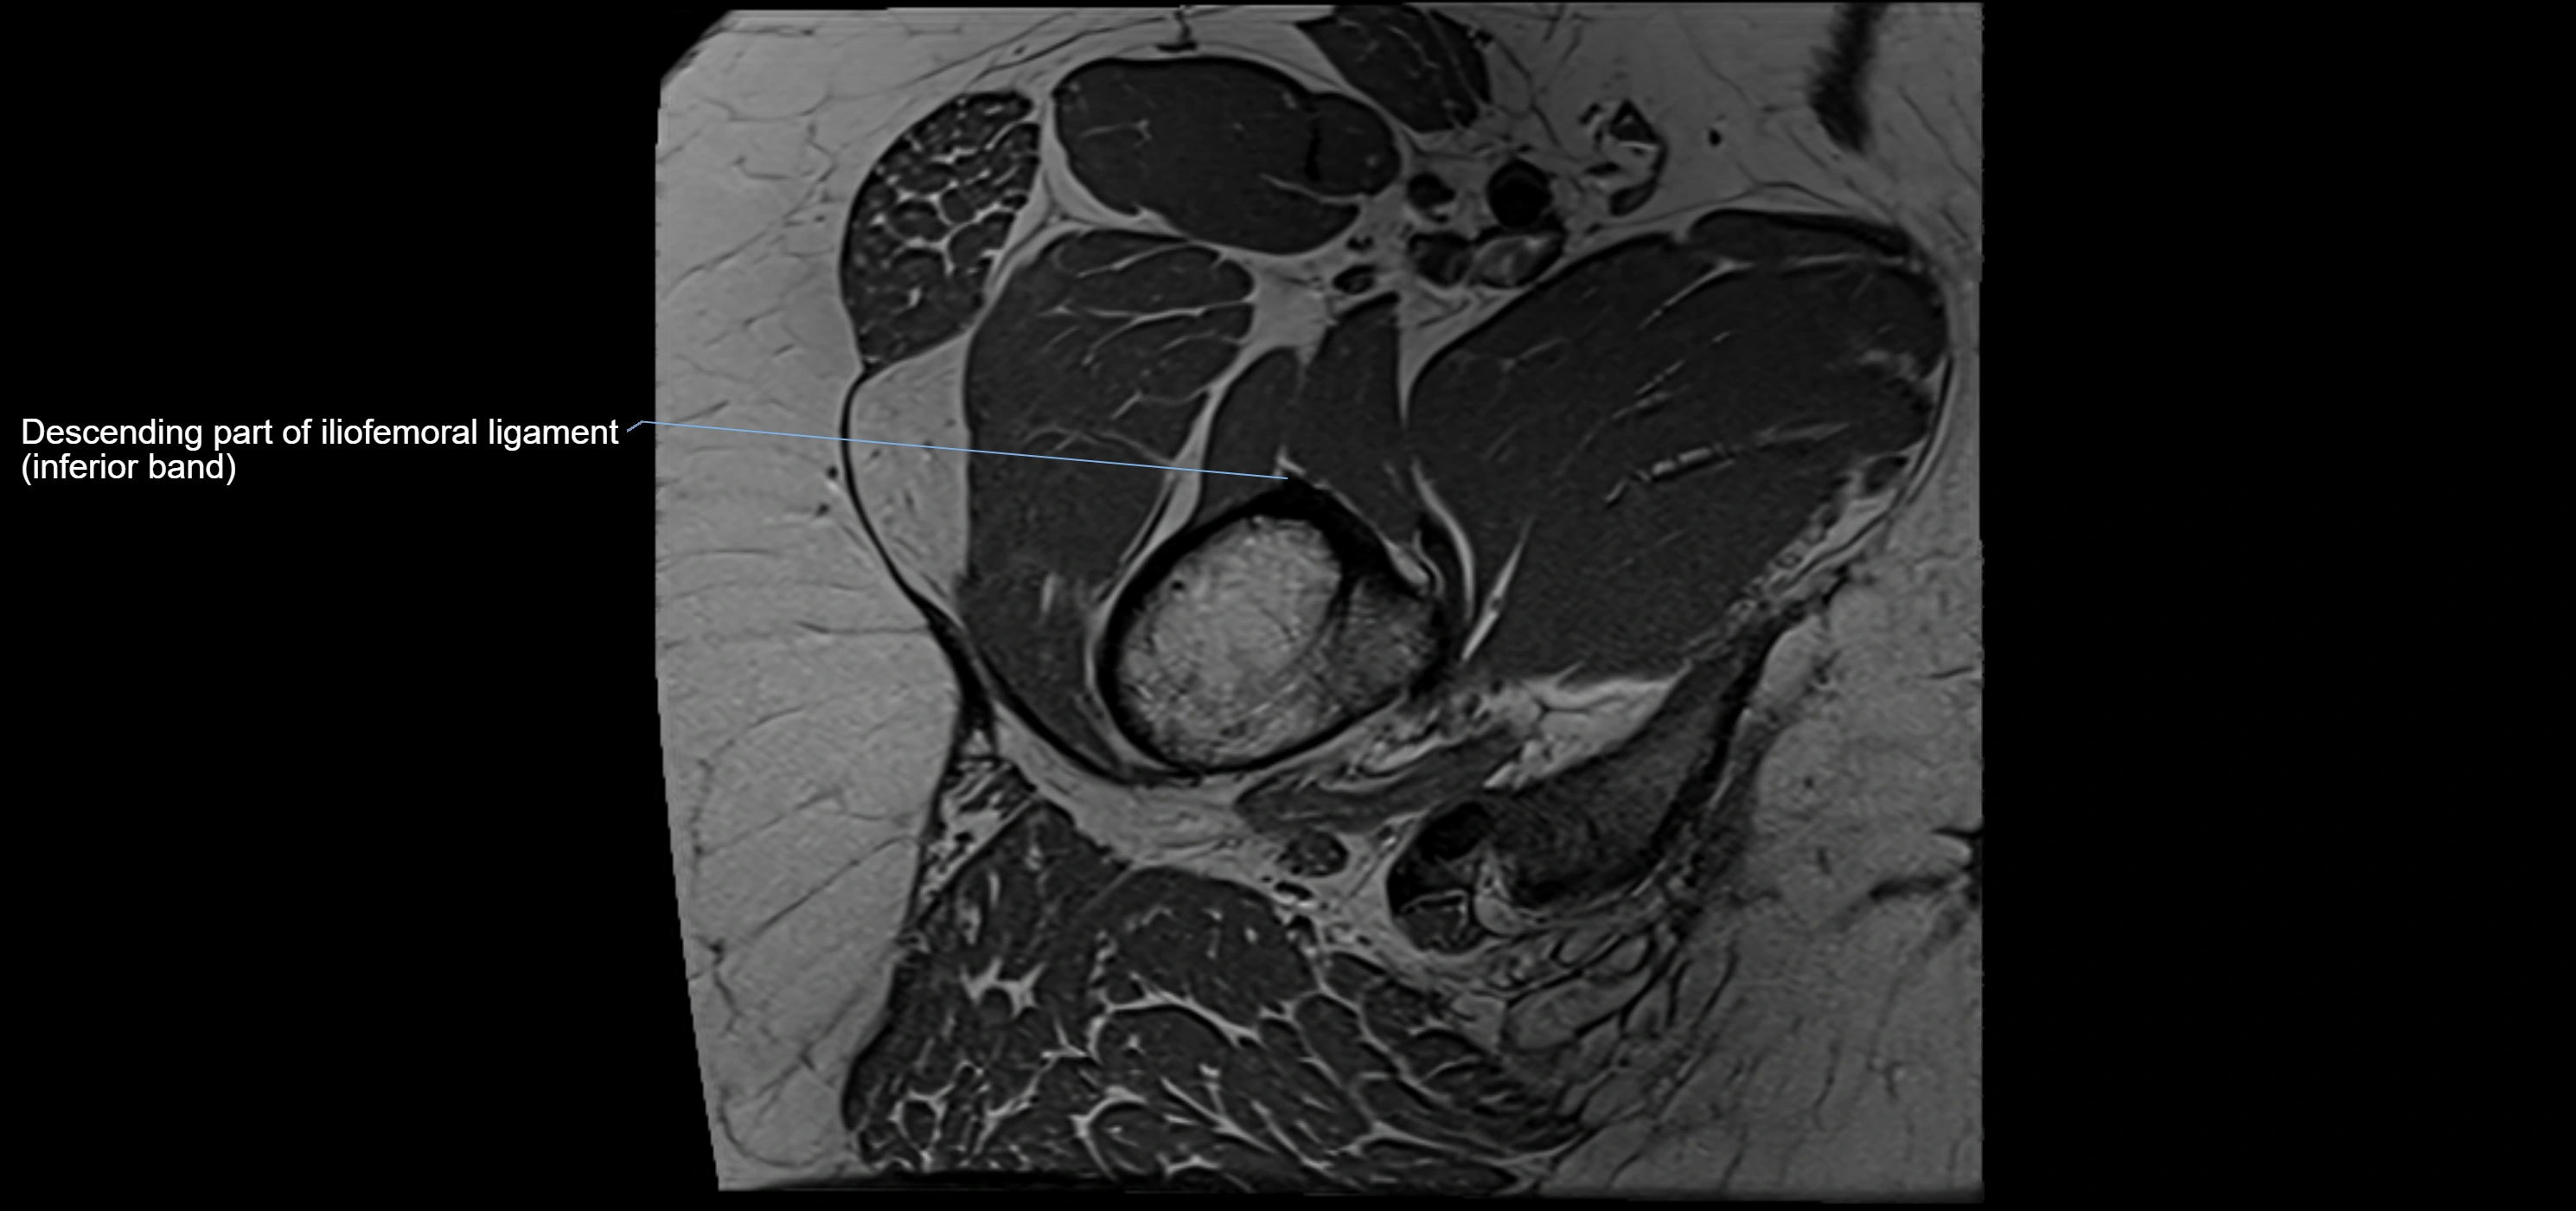

The acetabular labrum is a fibrocartilaginous ring that surrounds the rim of the acetabulum in the hip joint. It deepens the hip socket, increases joint stability, and maintains a suction seal that preserves negative intra-articular pressure. Structurally, the labrum transitions from hyaline cartilage of the acetabulum to dense fibrocartilage at its free edge.

It is triangular in cross-section, with its base attached to the acetabular rim and its apex projecting toward the femoral head. The labrum is most robust superiorly and anteriorly, where load bearing is greatest, and relatively thinner inferiorly.

Structure and Relations

• Superior and anterior labrum: thickest portions, stabilizing against anterior dislocation

MRI Appearance

T1-weighted images:

• Labrum: low signal intensity (dark)

• Surrounded by intermediate signal joint fluid (bright on arthrogram)

• Tears: linear or focal areas of intermediate-to-high signal interrupting labral continuity

MRI image

image